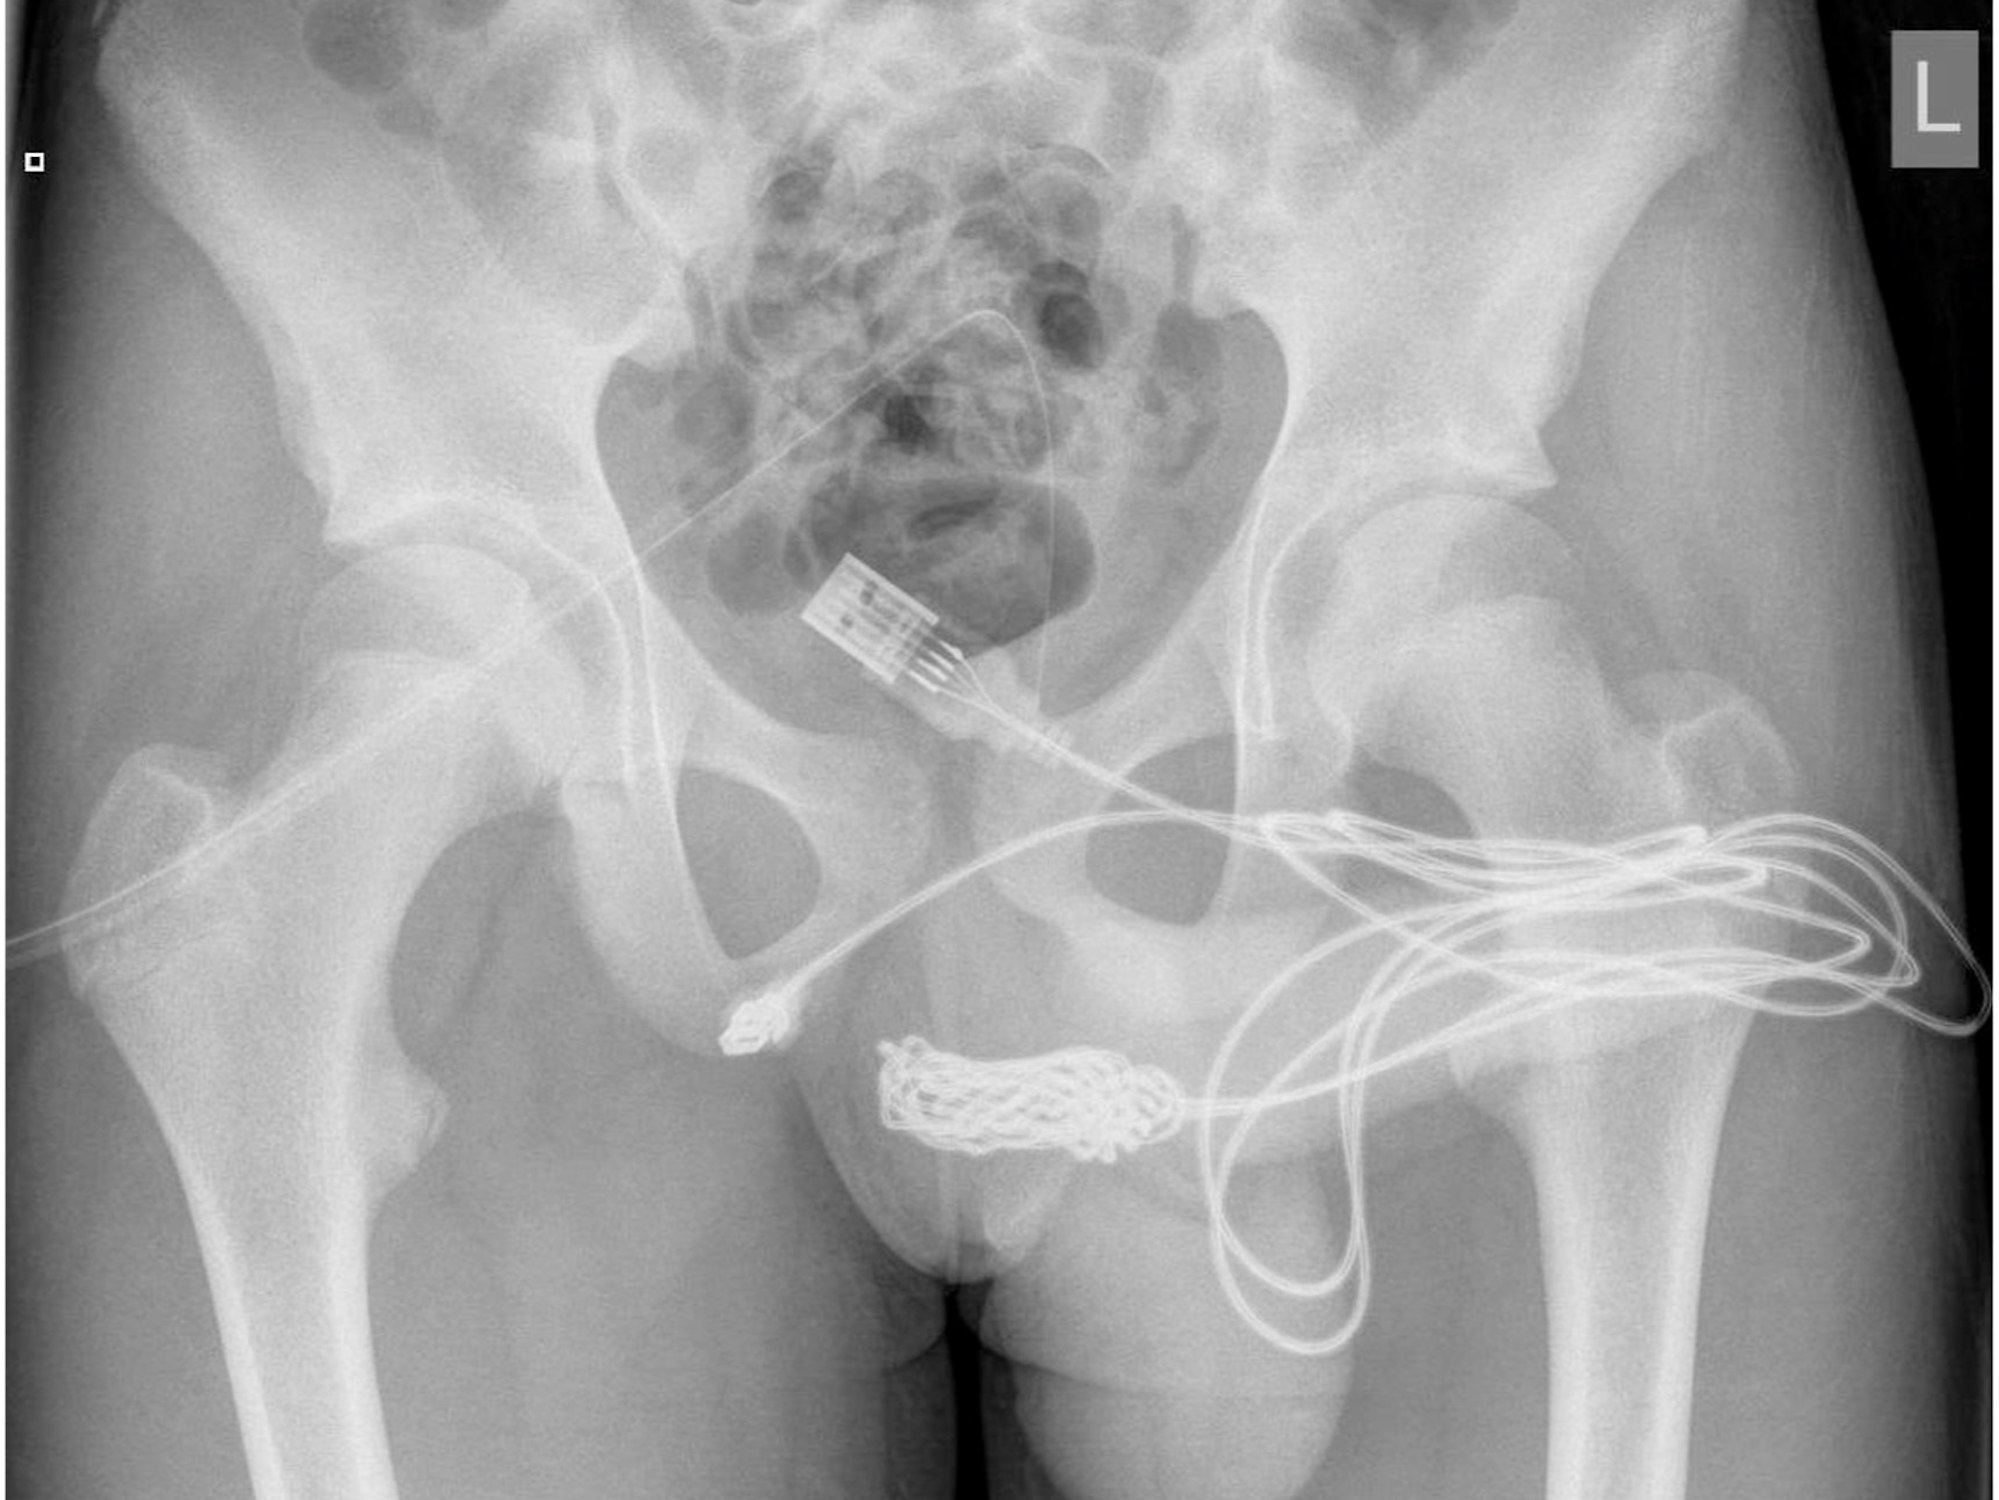

Auf dem Röntgenbild ist deutlich das verknotete USB-Kabel zu sehen, das im Körper des Jugendlichen stecken geblieben war. Der Teenager führte es bei einem fehlgeschlagenen sexuellen Experiment in seinen Penis ein.

Die unglaublichen Röntgenaufnahmen und ein medizinischer Bericht zu dem skurrilen Fall des Jugendlichen wurden jetzt in dem Fachmagazin „Urology Case Reports“ veröffentlicht.

Dort wurde er gründlich untersucht, es wurden Röntgenaufnahmen erstellt, er musste sich einer Blasenspiegelung unterziehen. Anschließend versuchten die Ärzte das Kabel herauszuziehen, allerdings scheiterten zunächst auch die Mediziner. Im Kabel hatte sich ein Knoten gebildet.